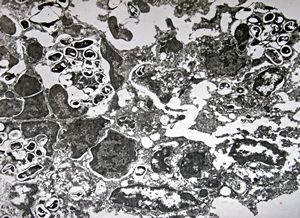

poxvirus - molluscum contagiosum